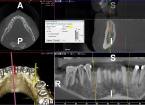

Progettazione virtuale / chirurgia guidata Un esempio della progettazione 3D di un intervento di posizionamento implantare SENZA BISTURI. Photogallery: